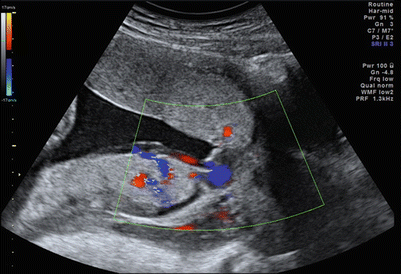

Fig. 12.11

Posterior placenta previa and anterior accessory placental lobe, with vasa previa

A low-lying placenta is a known risk factor for the development of vasa previa [53], and this factor must be kept in mind when following up on an earlier diagnosis of a low-lying placenta. Color Doppler imaging is recommended to assess the internal surface of the cervix to diagnose or exclude vasa previa as well as to identify the umbilical cord insertion to the placenta. [54] (Fig. 12.11).